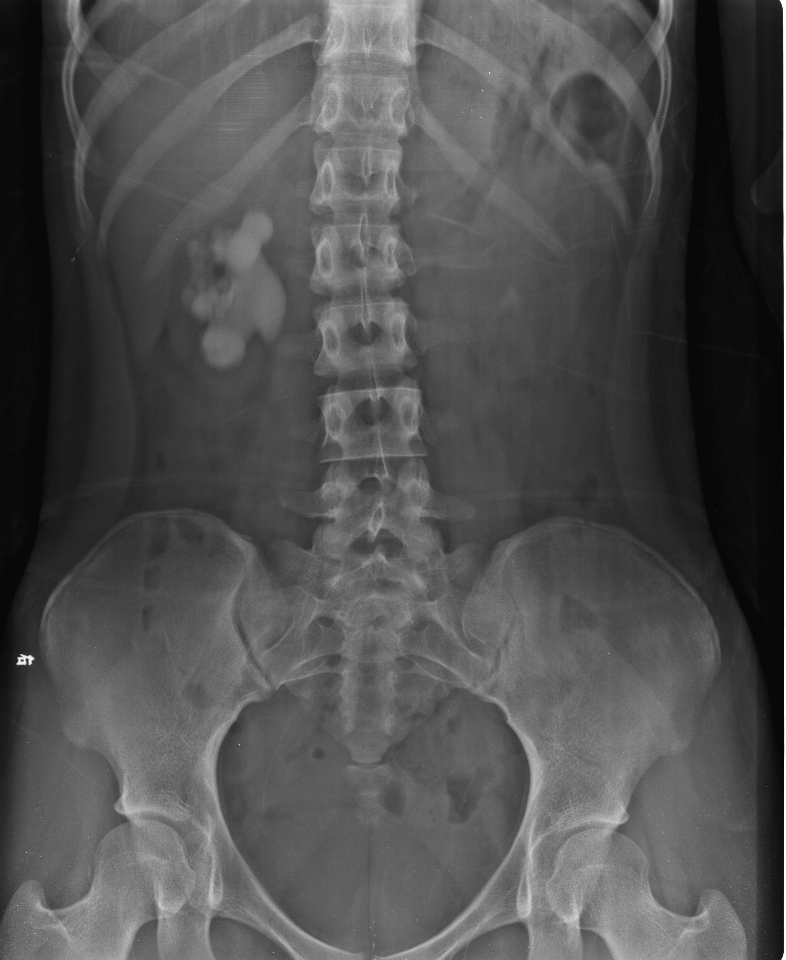

碎石前典型病例1                  碎石后典型病例1

碎石前典型病例2                  碎石后典型病例2